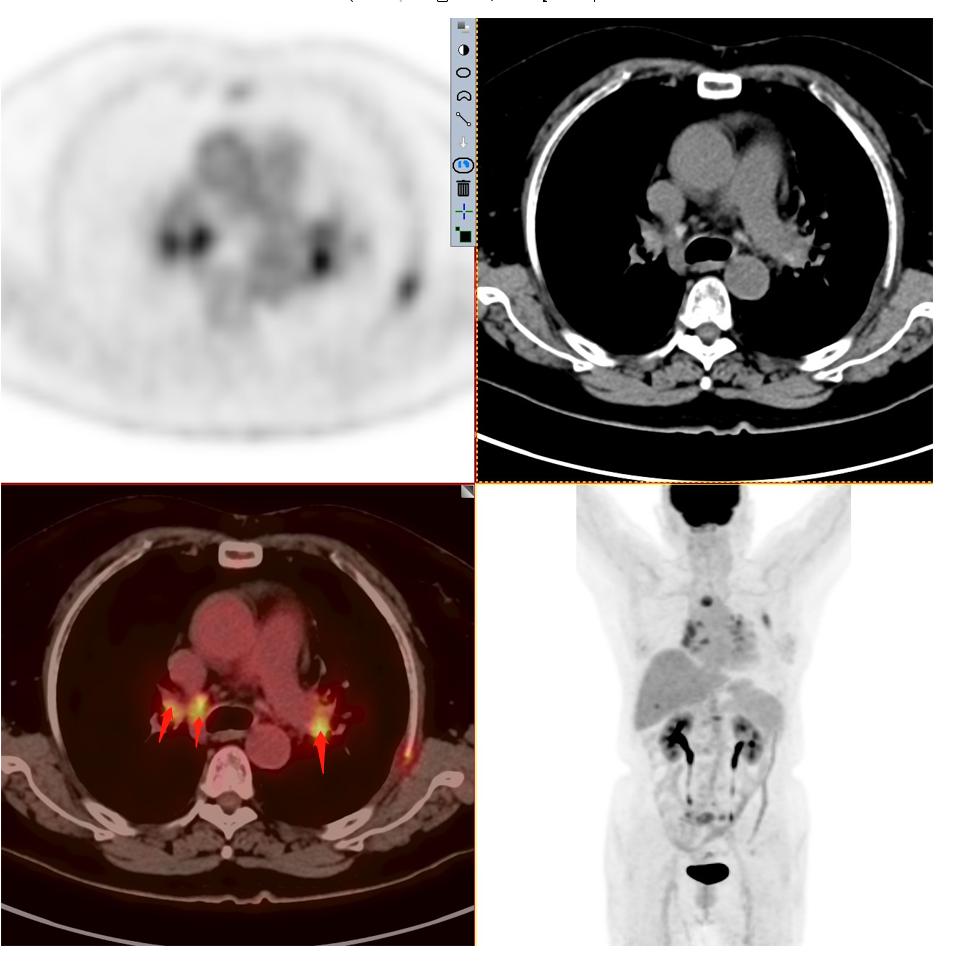

患者2:图3

发现纵隔多发淋巴结转移,并转移到对侧纵隔。